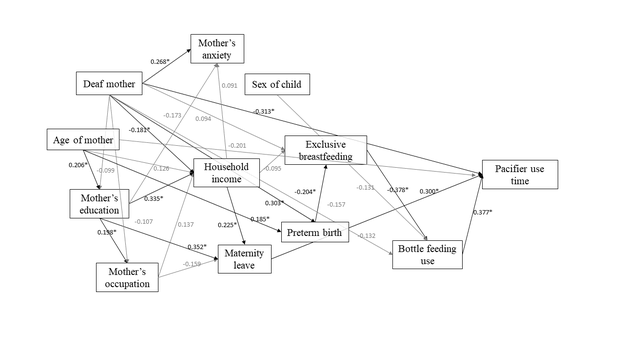

Pathway analysis of time of pacifier use by children whose mothers are hearing-impaired or have normal-hearing

Anxiety

Breastfeeding

Pediatrics

Statistics and epidemiology

Original article